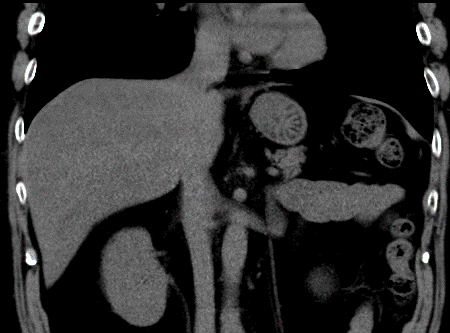

膵臓がん Pancreatic cancer

みなさんこんにちは!​ ブログ担当技師です。​ ​ だんだん暑くなってきましたね…